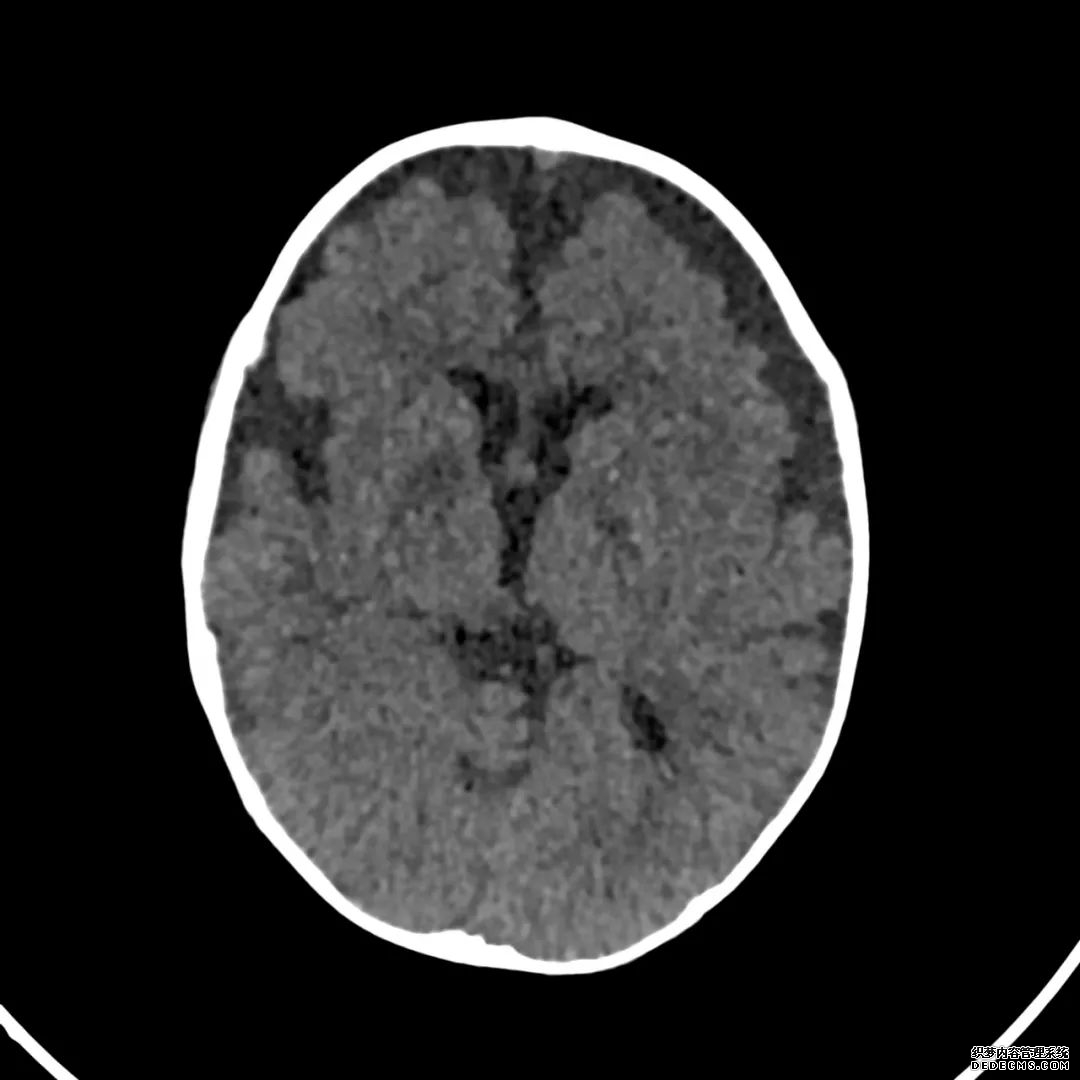

脑部CT检查显示扁豆状核内有略对称的低密度区。

脑MRI显示尾状核、扁豆状核和脑梗头部T2/FLAIR呈双侧对称异常高信号。扩散限制涉及这些区域,其特征是扩散加权DWI(B-1000)上的高强度,ADC图上相应的减弱强度。

印象:通过将这些成像模式与临床和实验室检查结果相结合,就有可能得出低血糖性脑病。

影像影响内囊后肢、大脑皮层(特别是枕叶和岛叶)、海马和基底节区,常是双边对称性的。